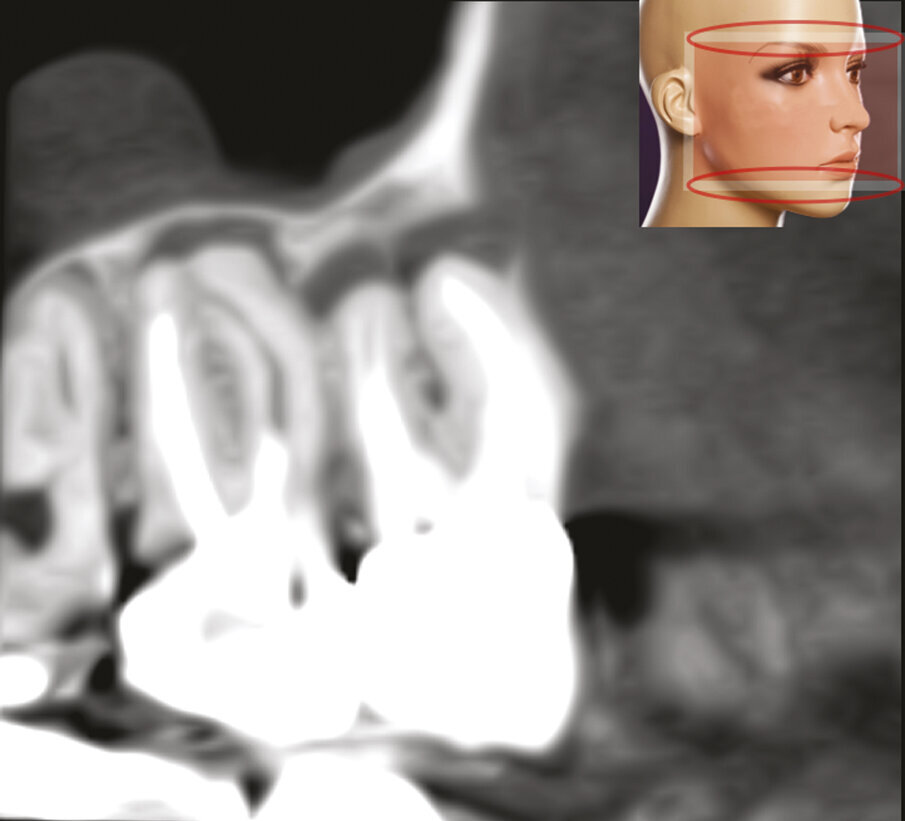

Fig. 1c - La CBCT mostra il riassorbimento dell’osso corticale adiacente la radice distovestibolare.

Fig. 2c - La CBCT mostra l’inclinazione distale della radice distovestibolare del primo molare.

Fig. 2d - La sezione coronale mette in evidenza il fatto che la radice distovestibolare del primo molare è vestibolare alla radice mesiovestibolare del secondo molare.

Fig. 2e - Le quattro sezioni assiali mostrano come la radice distovestibolare del primo molare sia vestibolare rispetto alla radice mesiovestibolare del secondo molare. Questa particolare situazione anatomica rappresenta una ovvia controindicazione all’approccio chirurgico.